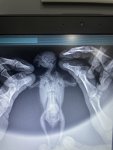

Bugün veterinere röntgen ve kontrol için tekrar götürdük ve bunlar röntgenleri.hekim bey karaciğerinde büyüme gözlemledi ve akciğerlere baskı yaptığından bu nedenle solunum sıkıntısı olduğunu söyledi.karaciğerin küçülmesi için ilaç tedavisi değil de pelet yem kullanmamızı söyledi.daha önce bu durumda olanlar varsa ya da bilgi sahibiyseniz bana yardımcı olabilir misiniz?5 gündür neftor kullanıyorduk keselim mi onu?

Karaciğer büyümesi ile ilgili zaten ilaç tedavisi değil de genelde takviyeler ile destekleme yapılır. Çok aşırı olmasa da evet var büyüme. Neftor u iki gün daha devam edip bırakabilirsiniz. Sadece pelet yem ile karaciğer küçülmez. Kaldı ki pelet yeme kuşlar alışma konusunda inatçı oluyorlar. Ben sanmıyorum pelet yemi yiyeceğini. Karaciğeri destekleyici takviyeler ile sürece devam edin.